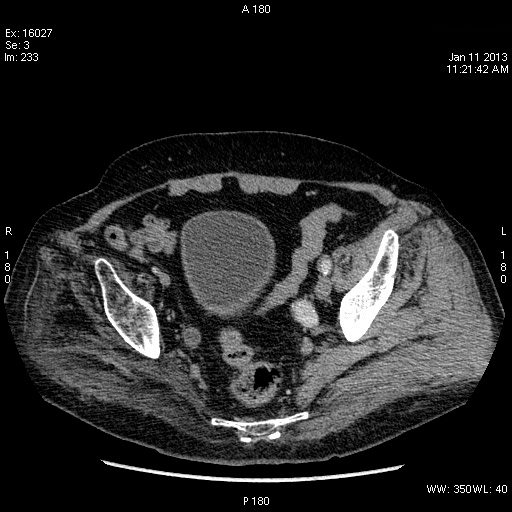

Пожилой человек с аневризмой брюшного отдела аорты.

Да, переходноклеточная опухоль нижней трети правого мочеточника, вторичный гидроуретеронефроз.

КТ

se001.jpg

se002.jpg

se006.jpg